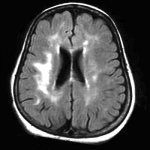

Недостаток сосредоточенности и концентрации является неврологическим состоянием. Исследования сканирования мозга показывают, что люди с этой патологией имеют нейронные цепи, которые немного другие, чем у обычных людей. Физические и химические различия в мозге влияют на исполнительное функционирование. Это означает, что людям с синдромом гиперактивности гораздо сложнее сконцентрироваться и отрегулировать свое поведение.

- сканирования мозга (МРТ);

Нейропсихологические механизмы СДВГ рассматриваются с позиций нарушений (незрелости) функций лобных долей головного мозга, прежде всего — префронтальной области. Проявления СДВГ анализируются с позиций дефицита функций лобных и префронтальных отделов мозга и недостаточной сформированности управляющих функций (УФ). Пациенты с СДВГ обнаруживают «управляющую дисфункцию». Развитие УФ и созревание префронтальной области мозга представляют собой длительные процессы. Значимыми компонентами УФ, которые страдают при СДВГ, являются: контроль импульсов, поведенческое торможение (сдерживание); организация, планирование, управление психическими процессами; поддержание внимания, удерживание от отвлекающих факторов; внутренняя речь; рабочая (оперативная) память; предвидение, прогнозирование, взгляд в будущее; ретроспективная оценка прошедших событий, допущенных ошибок; изменение, гибкость, способность к переключению и пересмотру планов; выбор приоритетов, умение распределять время; отделение эмоций от реальных фактов.